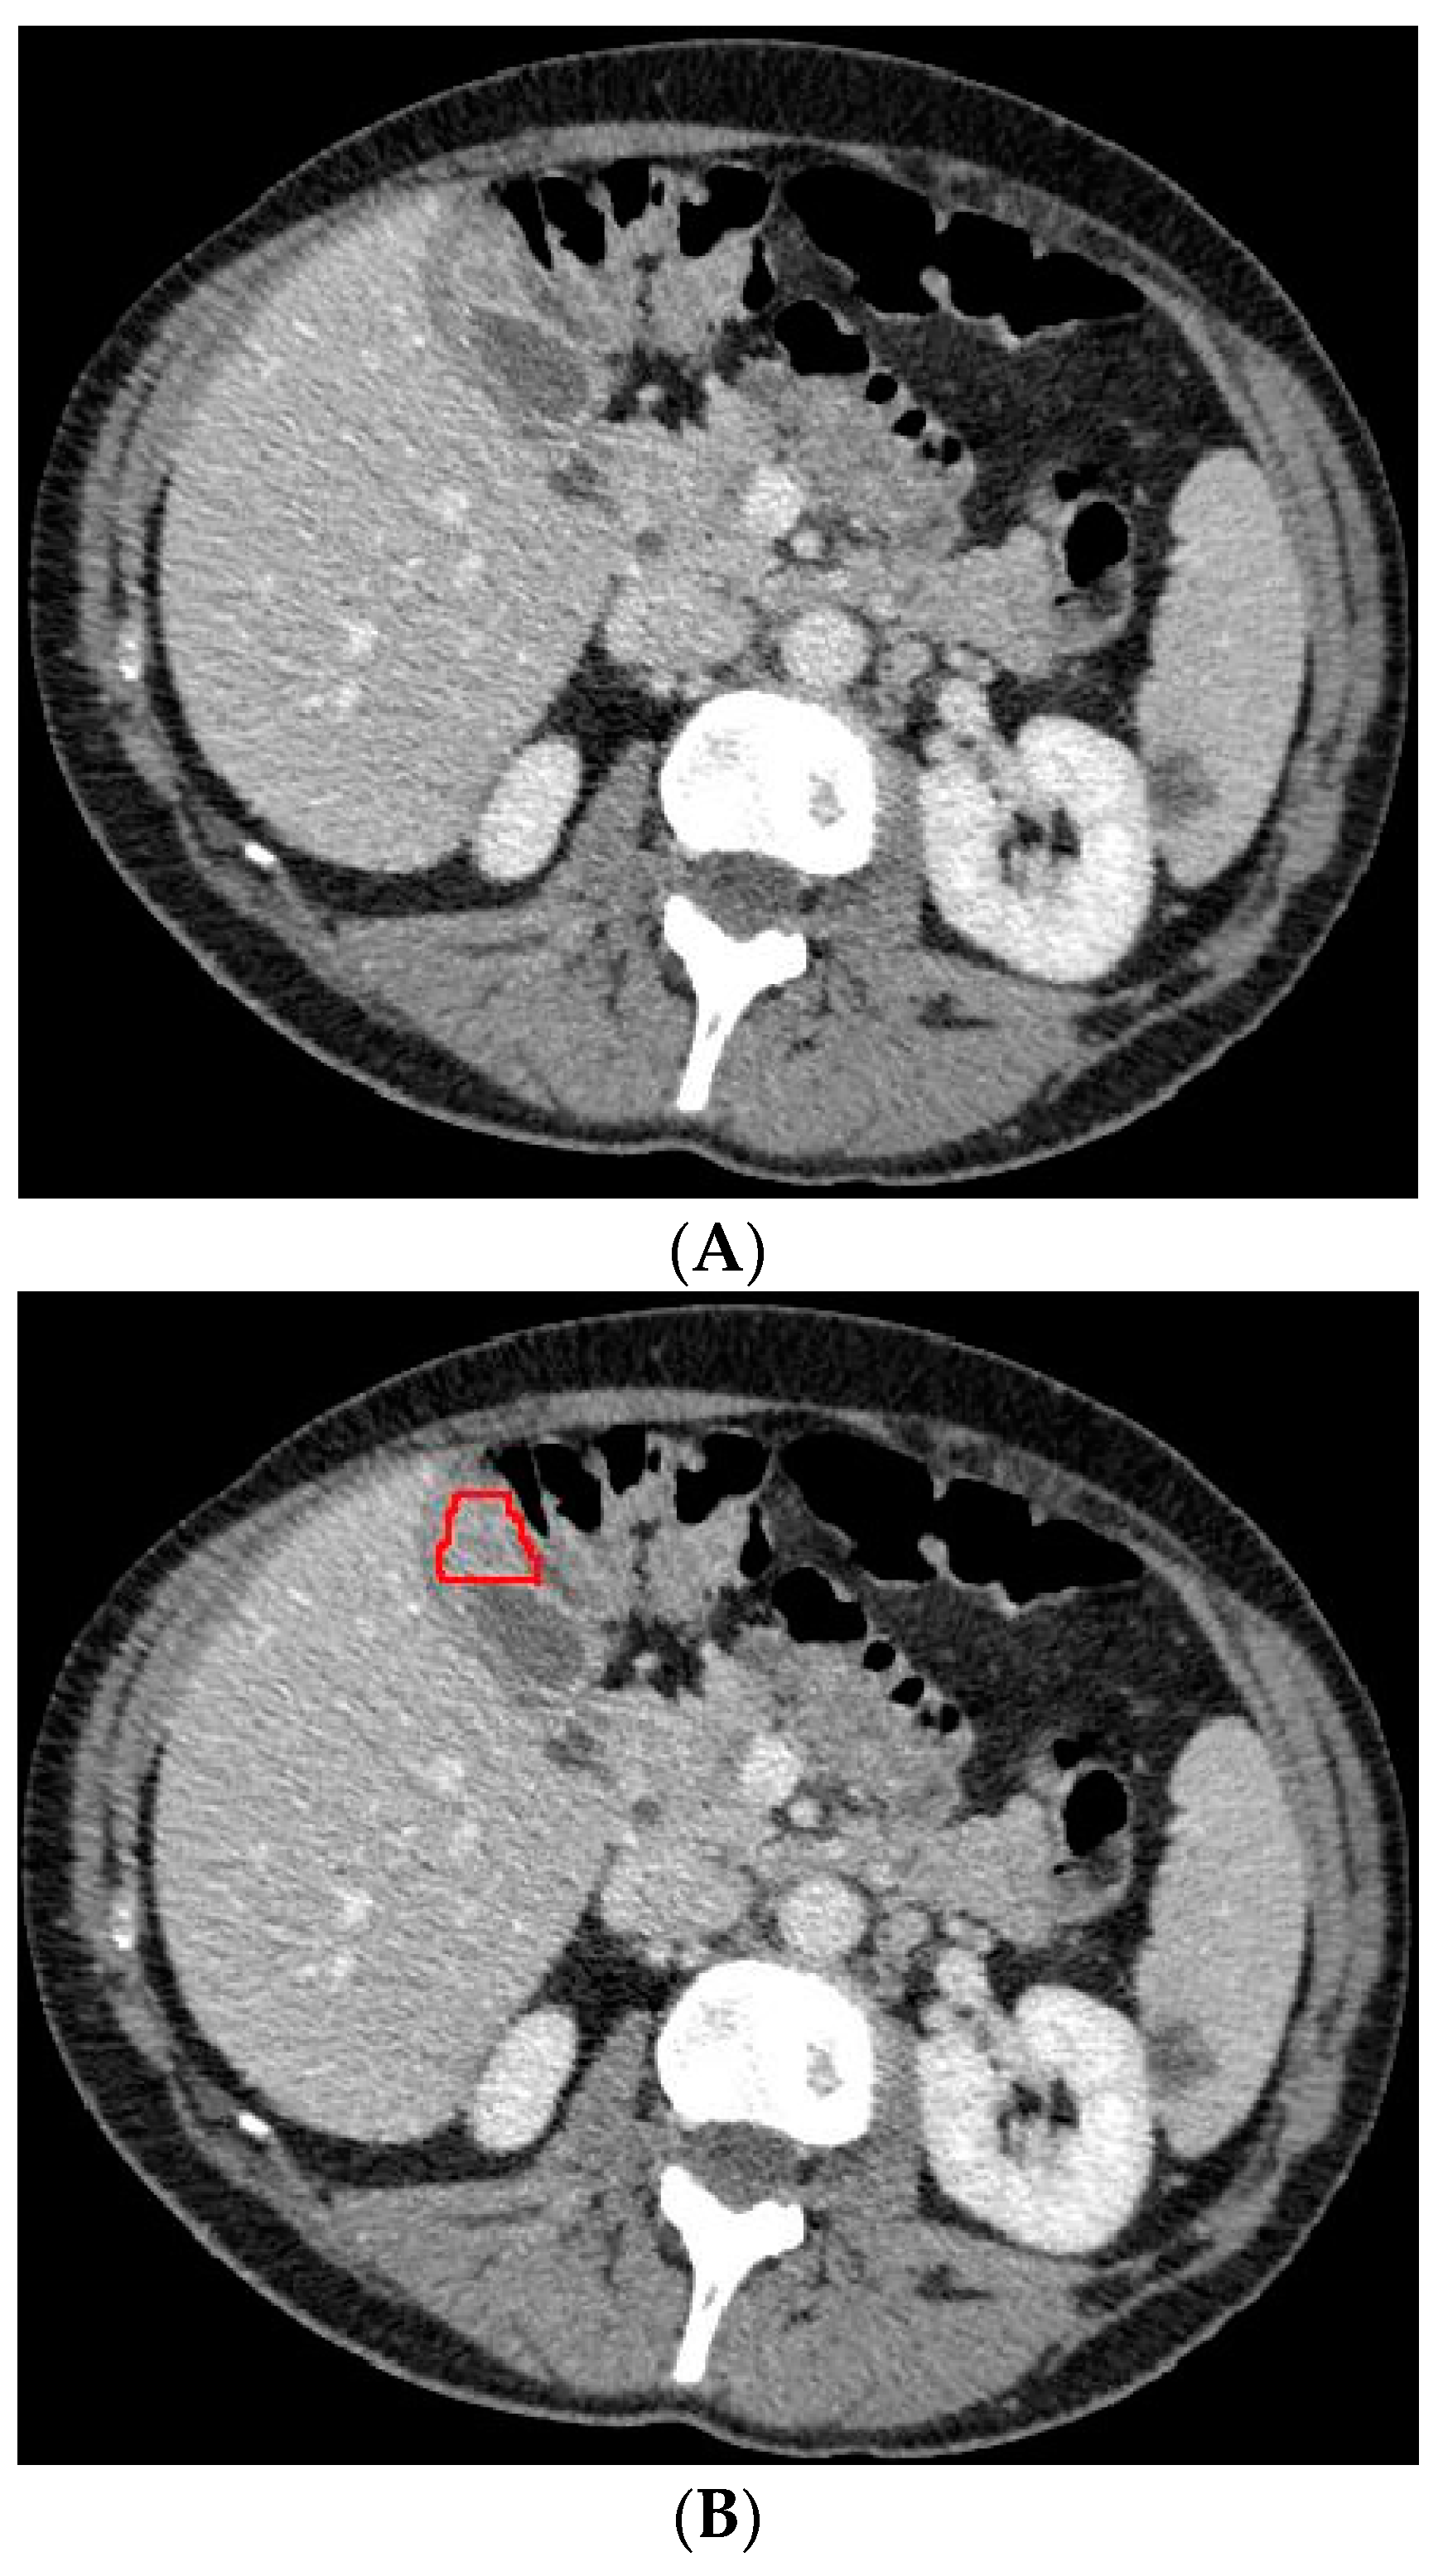

2.3. Deep Learning Model Based on Gallbladder and Liver Parenchyma

In a previous study, the suspicion of invasion of adjacent liver parenchyma was observed to be positively related to GBC [5]. Therefore, in addition to using only the gallbladder on CT images when training the deep learning model, a separate analysis was performed to investigate whether the combination of the gallbladder and adjacent liver parenchyma could increase the performance of the deep learning model when differentiating between GBC and benign gallbladder disease. The segmentation of a 2 cm rim of liver parenchyma adjacent to the gallbladder was automatically generated and adjusted by an experienced abdominal radiologist if necessary. The adjacent liver parenchyma was combined with the segmented gallbladder as training data for the deep learning model. Figure 4 shows examples of input CT images with segmentation of both the gallbladder and 2 cm of adjacent liver parenchyma. The deep learning model based on the combination of the gallbladder and adjacent liver parenchyma was trained and tested by the same methodology as described for the model solely based on the gallbladder.